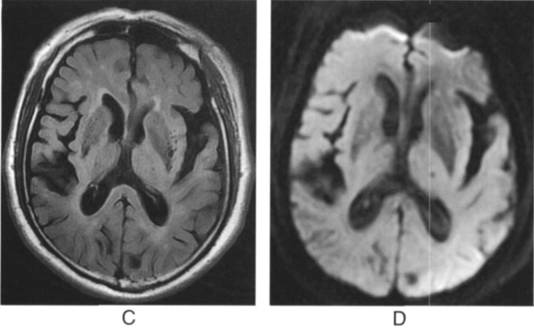

A.横断位T1WI显示双侧基底节多发斑点状低信号灶;B.T2WI显示高信号C.FLAIR成像显示为脑脊液信号,其周围脑组织信号正常D.DWI显示无弥散受限